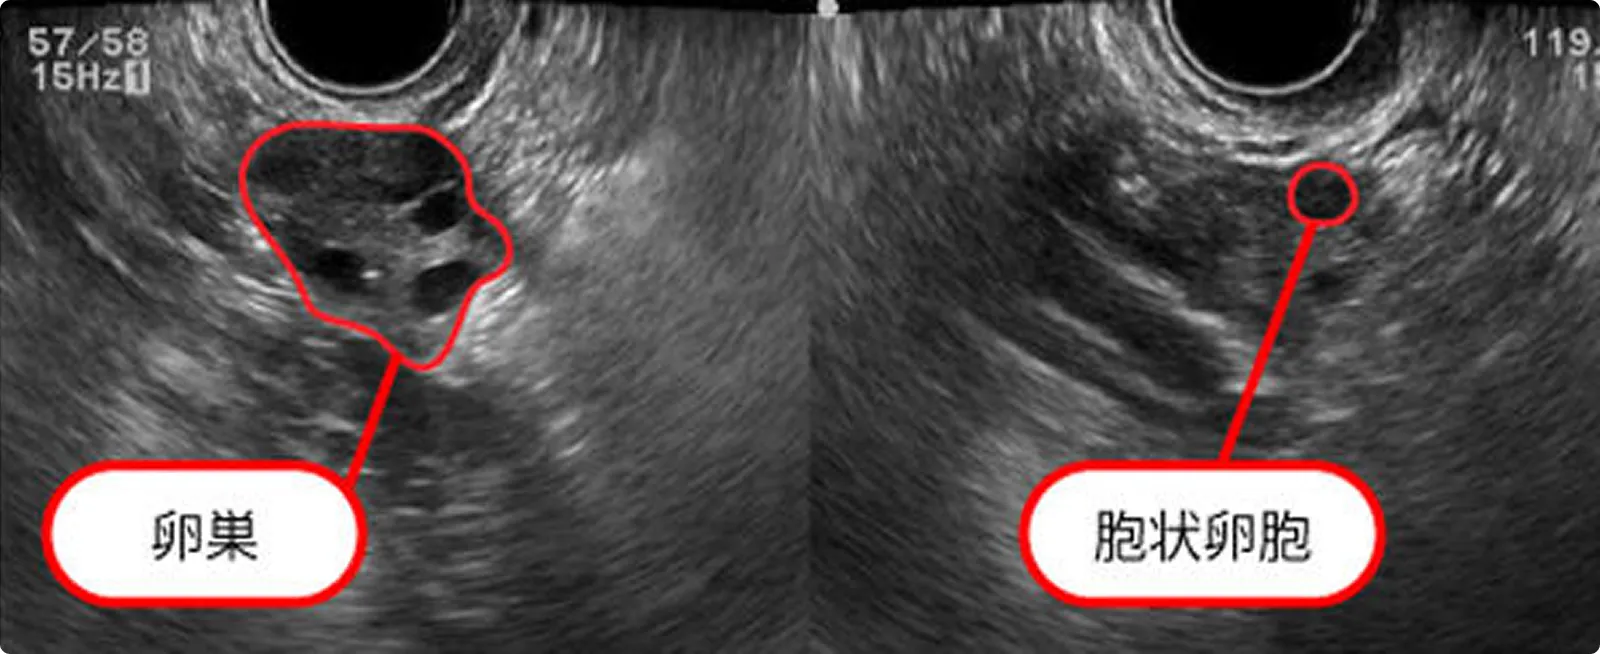

月経中

月経周期3日目の子宮内膜

腺上皮も間質細胞もまだ増殖しておらず薄い。

月経周期3日目の胞状卵胞

卵巣の中に黒く見えるものが胞状卵胞です。生理中の胞状卵胞の数は卵巣予備能を反映します。